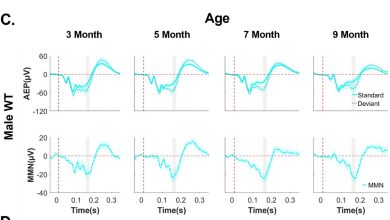

Sexo e idade moldam a progressão da doença de Batten, segundo estudo de ondas cerebrais

Camundongos WT de ambos os sexos apresentaram respostas MMN robustas de duração auditiva. Crédito: Jornal de Distúrbios do Neurodesenvolvimento (2025).…